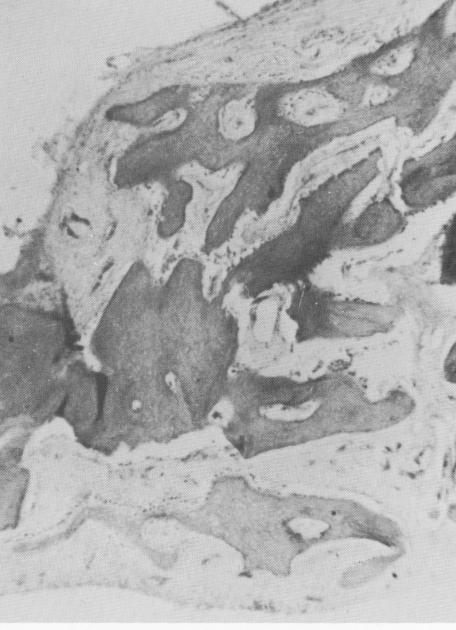

Fig. 4-76. The bony bridge tissues are healthy and free from unfavorable reactions. (Courtesy M. Hodosh.)

2 Healthy bony bridge tissues around crystalline implant